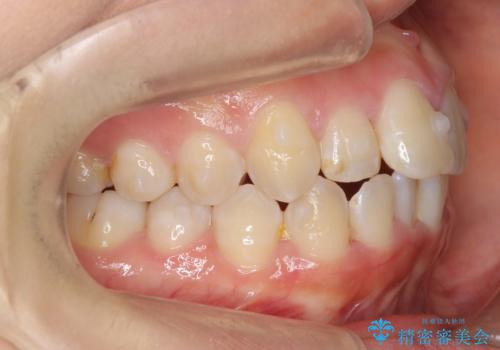

上下の前歯のがたつき 歯を抜かずに矯正

- 上下の前歯のがたつきを主訴に来院。

歯を抜かずに前歯を揃えています。

奥歯を後ろに下げたりなどはしていません。

奥歯を外に広げ、前歯中心に歯を少し削っていますが、健康には問題ない範囲で行なっています。